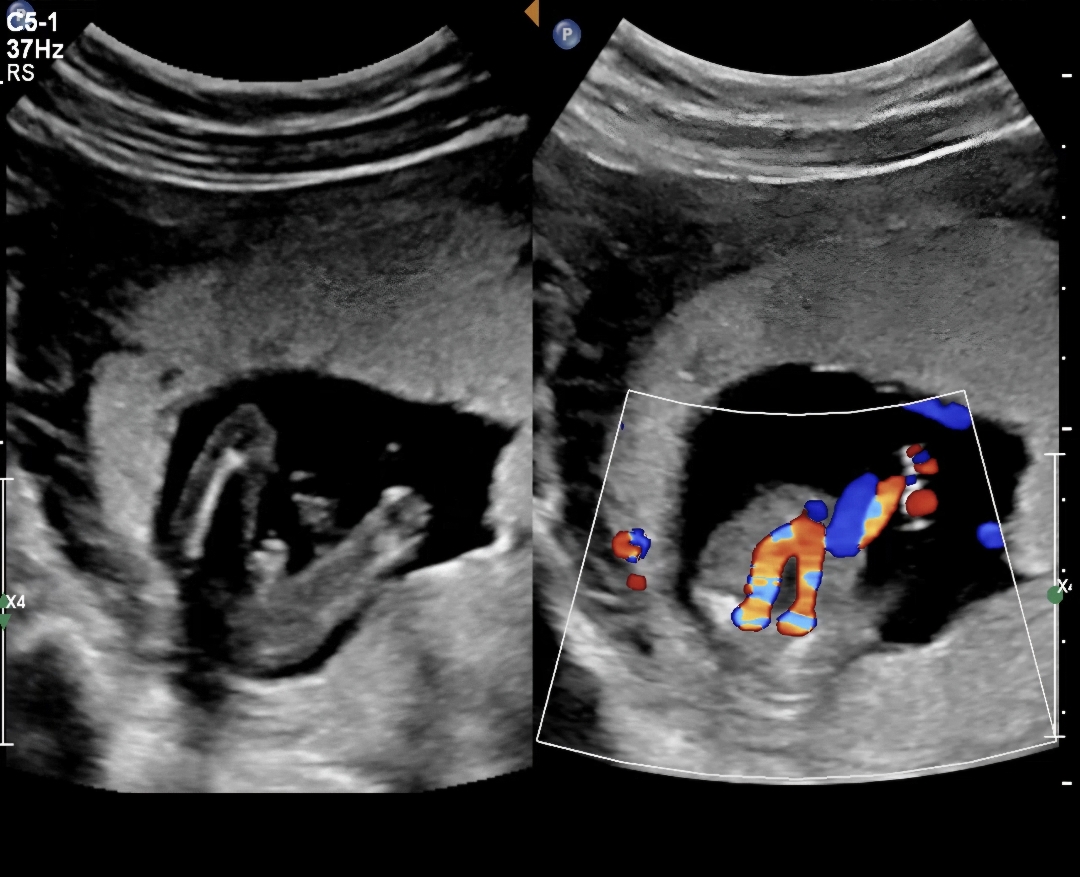

15주 2일차 초음파

오늘 초음파보고왔는데 확신의 아들이겠죠🫢🩵

아들맞네요